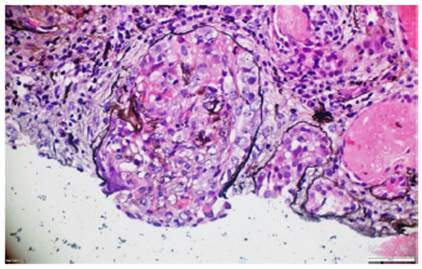

La biopsia de piel de la lesión ulcerativa en muslo izquierdo tuvo un reporte de patología que mostró abundante infiltrado inflamatorio mixto de predominio polimorfonuclear supurativo, con áreas de ulceración extensa, tejido de granulación con proliferación de vasos y abundantes histiocitos. Adicionalmente, la biopsia renal reportó presencia de medialunas fibrocelulares en más del 50% de los glomérulos, proliferación de células mesangiales e inmunofluorescencia negativa para complejos inmunes (figs. 5 y 6).

Figura 5 Metenamina de plata. Glomérulos con presencia de semilunas fibrocelulares y necrosis fibrinoide en el penacho glomerular. 10x.

Figura 6 Metenamina de plata. Semiluna fibrosa con destrucción de la membrana basal glomerular y reemplazo de células epiteliales por fibroblastos en un proceso cicatricial. 40x.